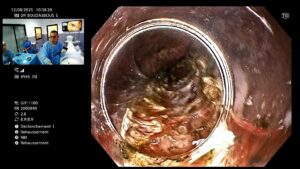

🔍 Déroulement de la procédure

- Réalisée sous anesthésie générale.

- Un endoscope flexible est introduit par la bouche.

- Le médecin crée un tunnel sous la muqueuse œsophagienne.

- Il sectionne les fibres musculaires du SIO responsables de l’obstruction.

- Le tunnel est refermé avec des clips endoscopiques.